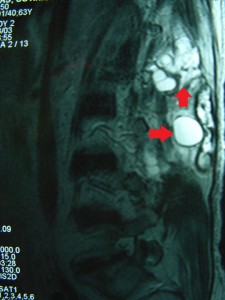

DSC00070_bakas_echinococos